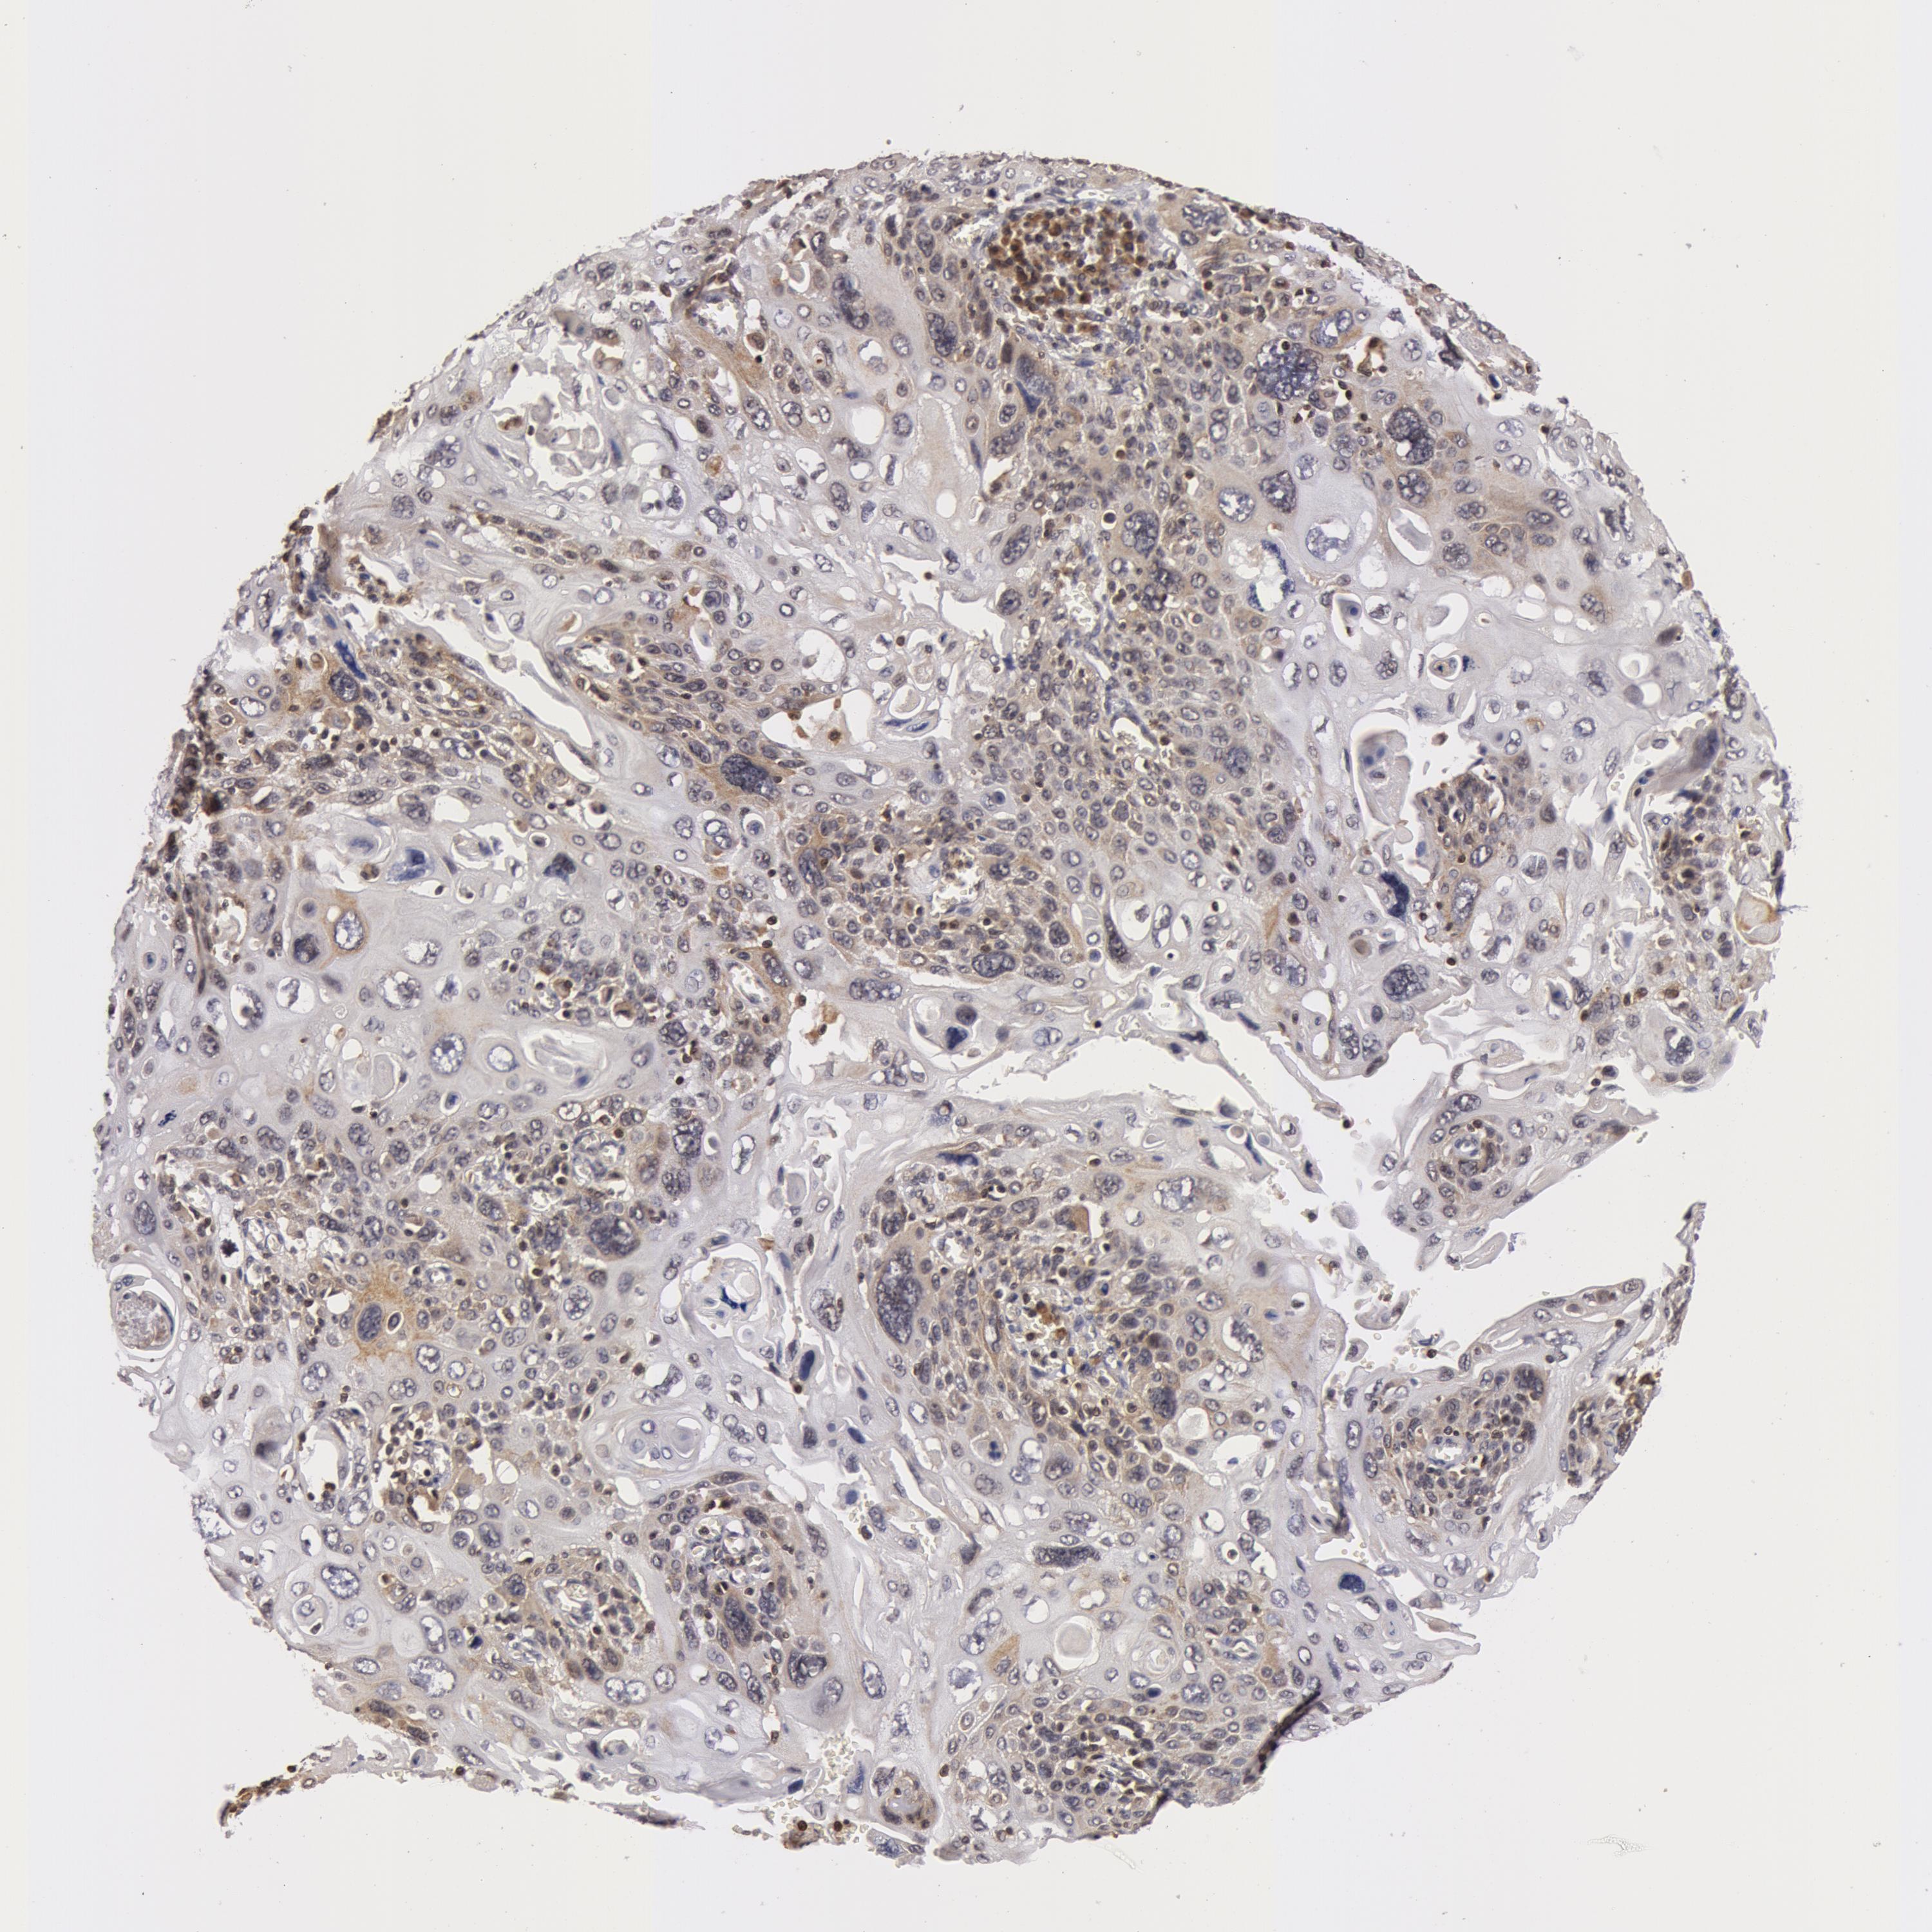

CERVICAL CANCER - Protein expressioni

A mouse-over function shows sample information and annotation data. Click on an image to view it in a full screen mode. Samples can be filtered based on level of antibody staining by selecting one or several of the following categories: high, medium, low and not detected. The assay and annotation is described here.

Note that samples used for immunohistochemistry by the Human Protein Atlas do not correspond to samples in the TCGA dataset.

Antibody stainingi

Antibody staining in the annotated cell types in the current human tissue is reported as not detected, low, medium, or high, based on conventional immunohistochemistry profiling in selected tissues. This score is based on the combination of the staining intensity and fraction of stained cells.

Each image is clickable and will lead to virtual microscopy that enables deeper exploration of all samples and also displays staining intensity scores, fraction scores and subcellular localization as well as patient and tissue information for each sample.

Antibody HPA001521

Staining

High

Medium

Low

Not detected

Intensity

Strong

Moderate

Weak

Negative

Quantity

>75%

75%-25%

<25%

None

Location

Nuclear

Cytoplasmic/membranous

Cytoplasmic/membranous,nuclear

Adenocarcinoma, NOS